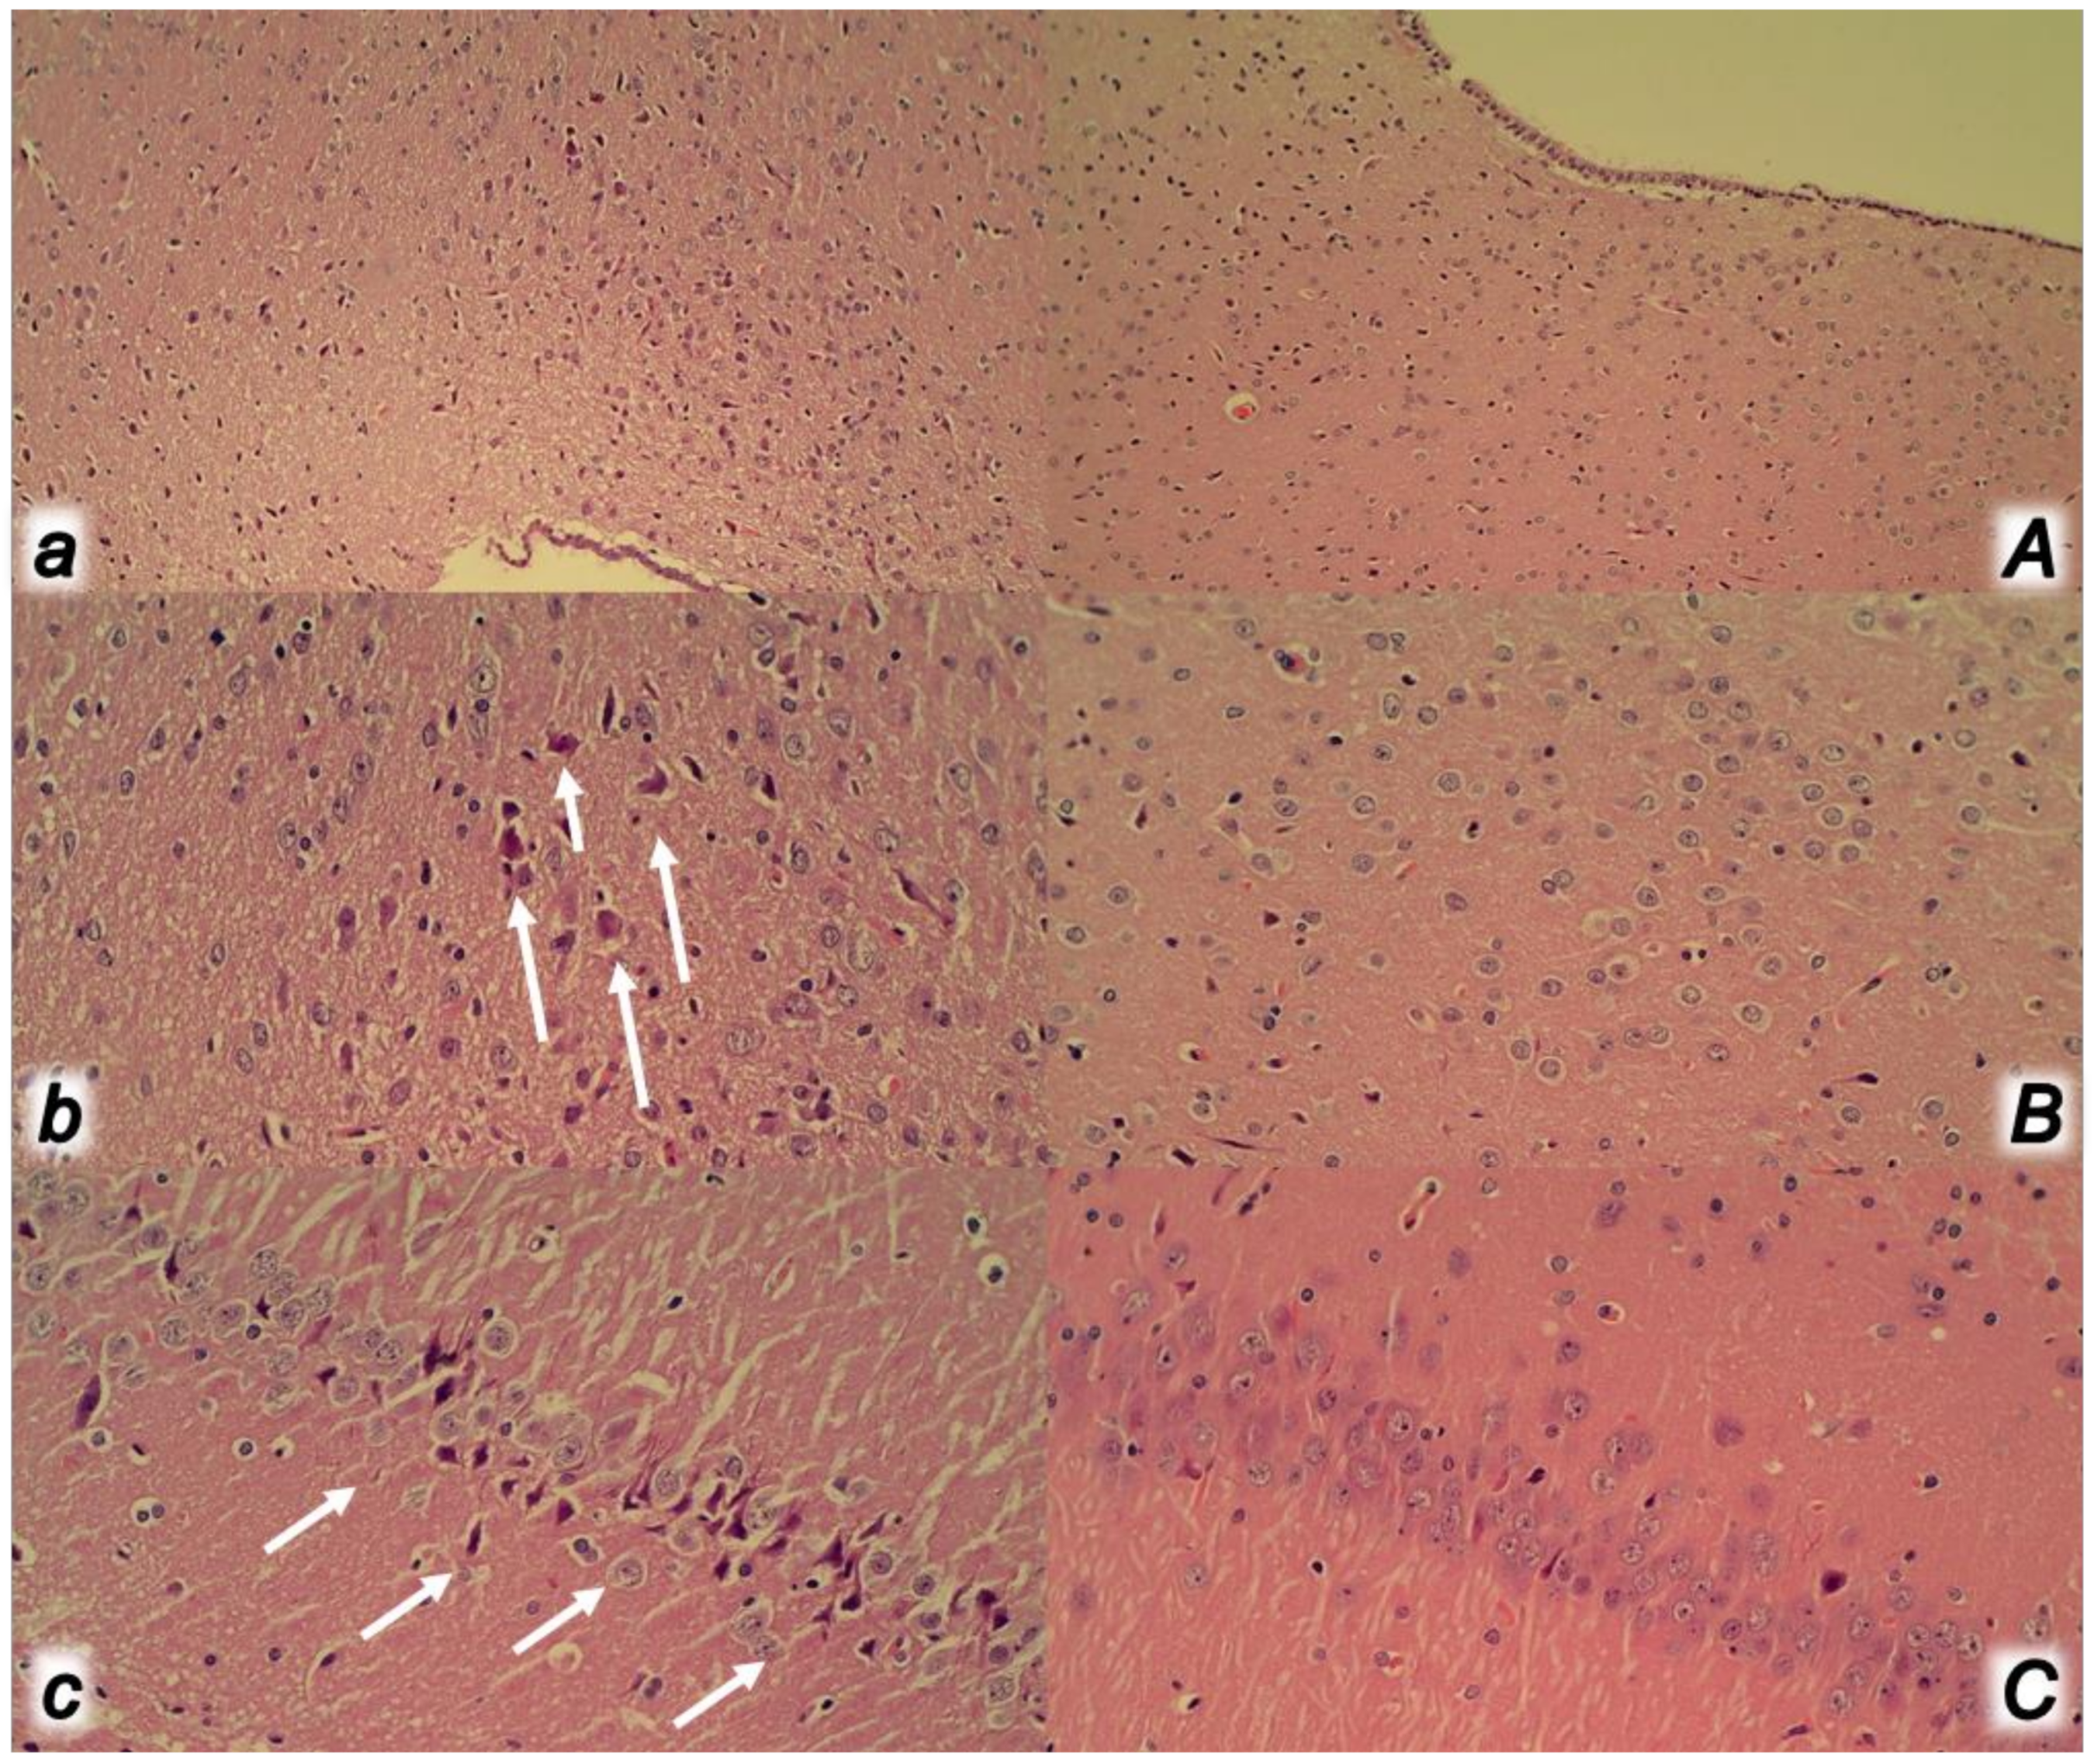

2.12. Microscopy

2.12.1. Lung Histology

2.12.2. Renal, Liver and Heart Histology

2.12.3. Gastrointestinal Histology

| Brain Area | Grading | Percent Area Affected | Morphological Changes |

| Cerebral and cerebellar cortex, hypothalamus, thalamus, hippocampus | 1 | ≤10 | Small, patchy, complete or incomplete infarcts |

| 2 | 20–30 | Partly confluent complete or incomplete infarcts | |

| 3 | 40–60 | Large confluent compete infarcts | |

| 4 | >75 | In cortex; total disintegration of the tissue, in hypothalamus, thalamus, hippocampus; large complete infarcts | |

| Cerebral and cerebellar cortex, hypothalamus, thalamus, hippocampus | 1 | ≤20 | A few karyopyknotic of neuronal cells |

| 2 | 50 | Patchy areas of karyopyknotic areas | |

| 3 | 75 | More extensive of karyopyknotic areas | |

| 4 | 100 | Complete infarction |